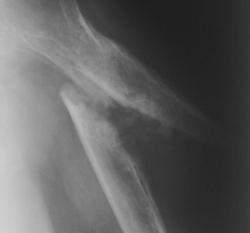

На "последней рентгенограмме превалирует угловое смещение отломков, имеет место некоторое смещение по ширине, если есть, то весьма незначительная ротация.

Края отломков, на последней рентгенограмме несколько склерозированы и зализаны, по сравнению с "первой рентгенограммой".

Конечно, прав Андрей Юрьевич, говоря об "интерпозиции мягких тканей" (мышц).

Патологические участки окостенения в "мягких тканях" (мышцах) свидетельствуют о том, что данный перелом, без надлежащего "хирургического вмешательства" никогда не срастется, ибо между отломками мышечные ткани, с выраженными дистрофическими изменениями и участками метаплазии, которое в последствии может быть отнесено к гетерогенному окостенению.

В области акромиального отростка - "остеопороз от бездействия, недогруза конечности", явления артроза в ключично-акромиальном сочленении.

Совершенно прав Андрей Юрьевич, говоря об "интерпозиции мягких тканей" (мышц).